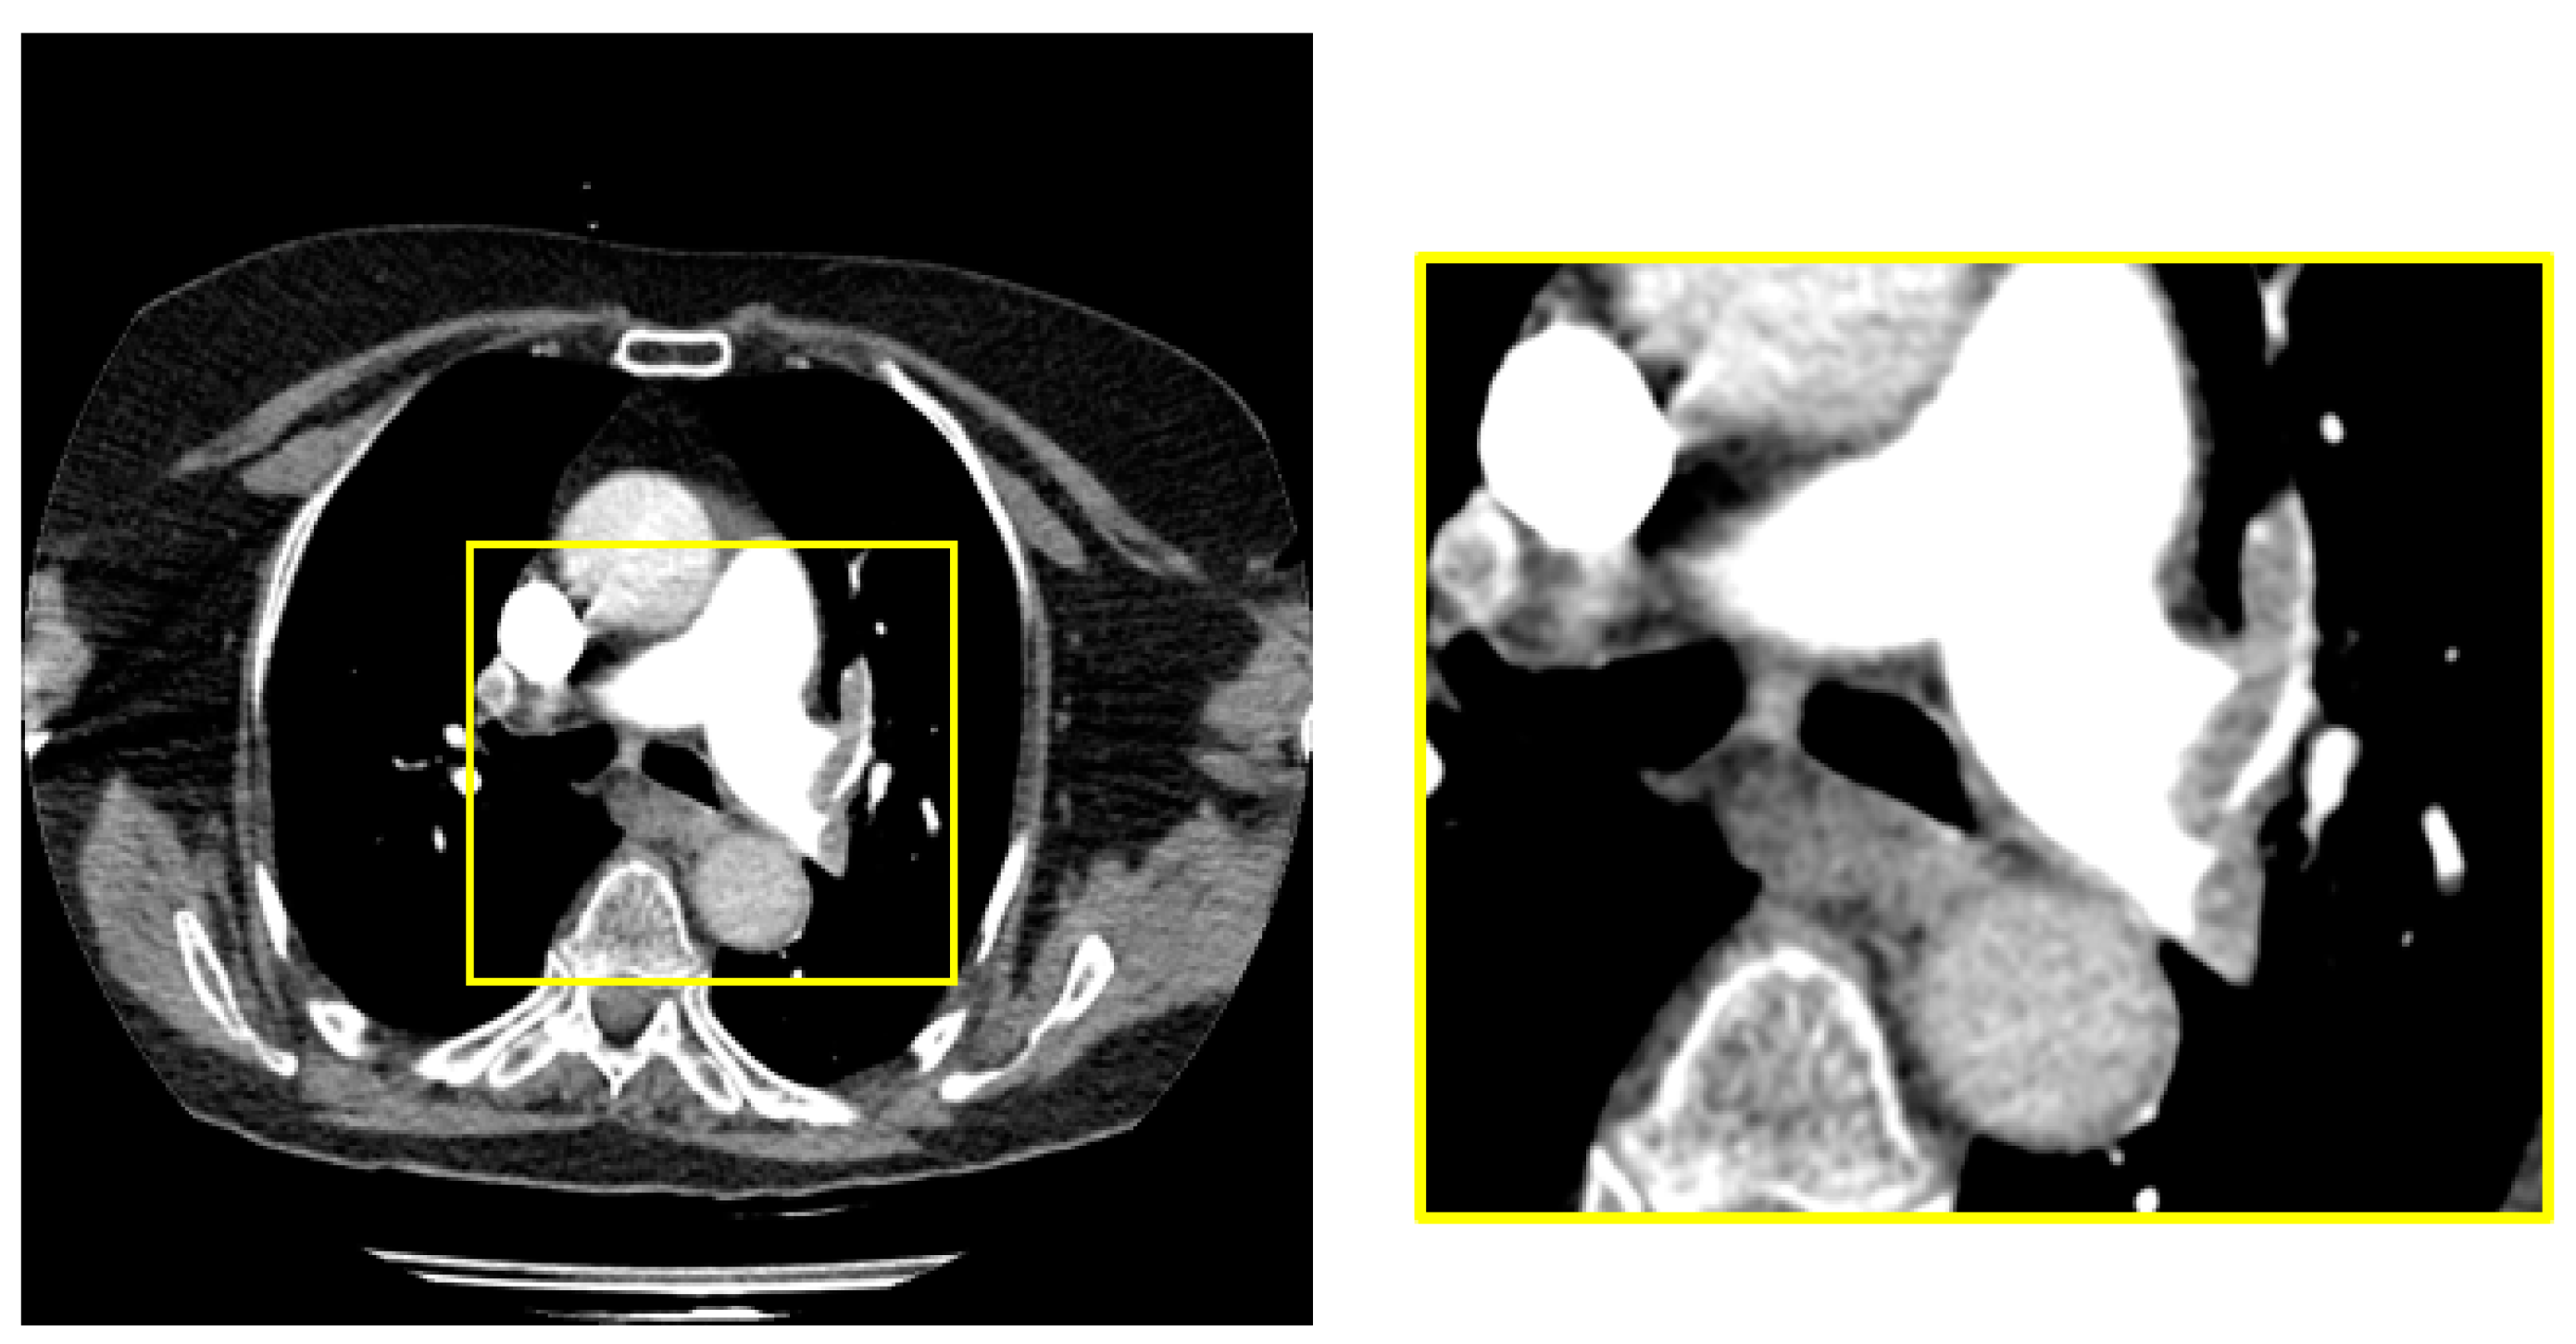

The dimensions of the raw images in the dataset are 1212 x 1212. PE is located in the middle region of all images in raw dataset. We obtained a 448x448 sub-image from the middle region of the raw image to cover the sections with pulmonary embolism. Figure 2 shows the raw image and sample subimage with PE.

Figure 2. Obtaining the middle chamber containing PE.